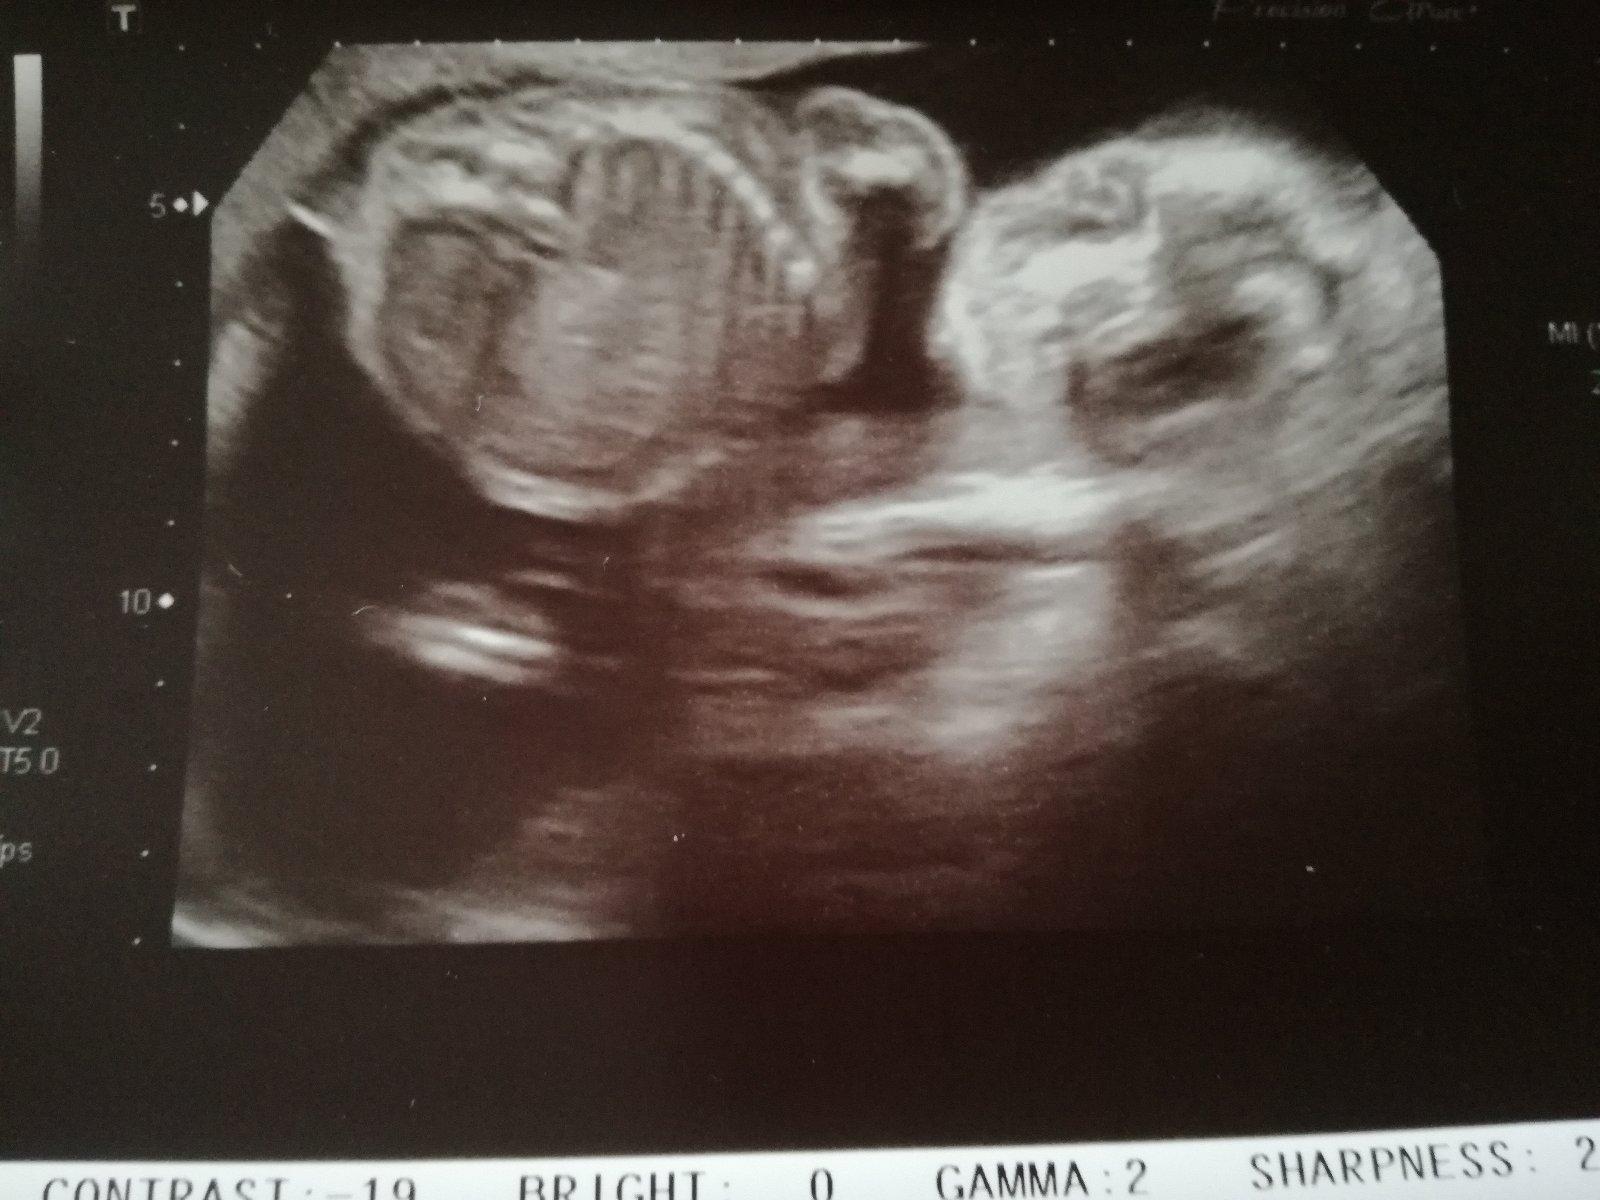

Je to holčička nebo chlapeček? Foto ultrazvuku

Jestli jsem se dobre zorientovala, pripadne mi to na holcicku, nevim. A dr rekla co?

Nejsem si úplně jistá, jestli je pohlaví na té fotce vidět právě. Ale je to chlapeček 🙂

@alhamdulillah pohlavní hrbolek bohužel není dobře vidět 😔

@pampeliska1 tipuji chlapecka..u holcicky by zrejme bylo videt "kavove zrno" .-)